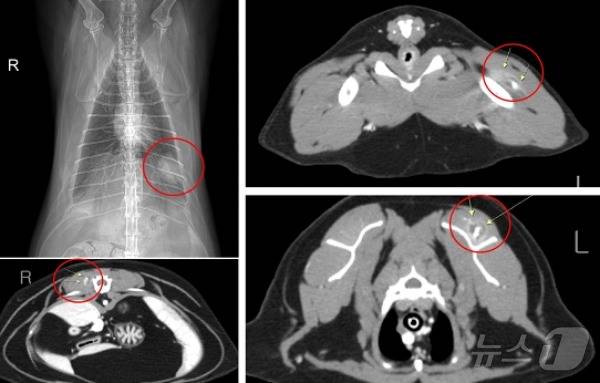

흉부방사선촬영 결과 좌측 폐후엽에 폐종양이 확인됐다. 전신 CT(컴퓨터단층촬영) 검사에서는 전신근육 내 다발성의 종양이 발견됐다.